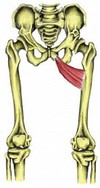

Give the (i) Origin (ii) Attachment (iii) Action and (iv) Innervation for TERNSOR FASICA LATAE.

(i) Anterior superior iliac spine; anterior part of iliac crest

(ii) Iliotibial tract, which attaches to the lateral condyle of tibia

(iii) SAME AS GLUT MED & MIN: Abduct and medially rotate thigh; keep pelvis level when ipsilateral limb is weight-bearing and advance opposite (unsupported) side during its swing phase

(iv) SAME AS GLUT MED & MIN: Superior gluteal nerve (L5, S1)